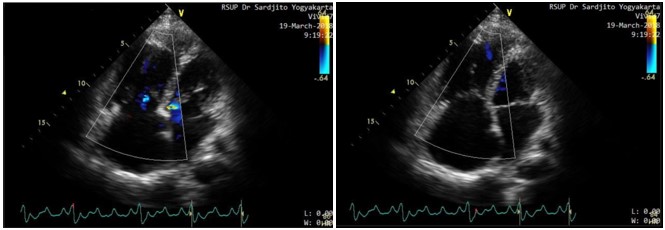

Background: Secundum type atrial septal defect (ASD) is the most common adult congenital heart disease. Hemodynamically, ASD result in a left-to-right shunt that causes right heart volume overload. This condition affects interventricular septal position and shape. Left ventricular (LV) eccentricity index (EI) suggests right ventricle (RV) overload when this ratio is >1.0. The aim of this study was to assess correlation between LV EI and mean pulmonary arterial pressure (mPAP) in secundum type ASD patients. Methods: We conducted a cross sectional study from ASD patients registry data. We enrolled subjects with secundum type ASD from the complete registry data. The LV EI was calculated from transthoracal echocardiography. The mPAP was measured by right heart catheterization as a gold standart. The correlation was performed by Spearman correlation test. Results: There were 40 adult secundum type ASD patients participated. The mean LV EI in enddiastolic was 1.55±0.39 and LV EI in end-systolic was 1.75±0.58. The median value of mPAP was 29 (12-99) mmHg. There was a moderate strength, positive and significant correlation between LV EI in end-diastolic and mPAP (r=0.37, p=0.018). The correlation was more significant and stronger between LV EI in end-systolic and mPAP (r=0.52, p=0.001). Conclusion: There was sufficiently strong and significant correlation between LV EI in both end-diastolic and end-systolic phase with mPAP in adult secundum type ASD.